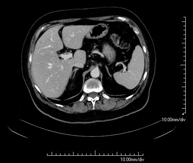

- Abdomen CT

Diagnostic test that involves obtaining high-definition anatomical images of the abdomen (liver, gallbladder, bile duct, pancreas, spleen, stomach, intestines, kidneys, vascular structures, bladder, uterus and ovaries, etc.) using CT (computed tomography) equipment. These images are then studied at a workstation capable of producing two-dimensional reconstructions in different spatial planes, and also 3D (volumetric) reconstructions. Most studies require the use of iodinated contrast to improve image definition.